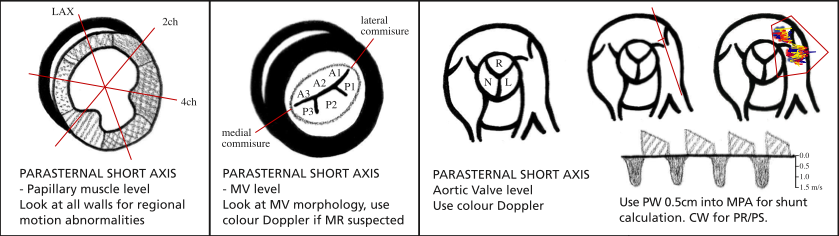

PSAX (Parasternal Short Axis)

From your best PLAX view rotate the probe 90 so the marker points towards the patient’s L shoulder. Sweep angle of probe to get views at aortic (anterior), MV, papillary and apex (posterior).

Narrow sector width and reduce depth to focus on area of interest.

Papillary level

2D

Inspect for:

- Papillary muscles (ant and post)

- LV wall thickness

- LV fx and RWMAs (see here for anatomy)

- RV size and fx

- Septal flattening

LV area in diastole and systole (ignoring papillary muscles) to calculate fractional area change (a measure of systolic function).

Colour

Interventricular septum for VSD.

Apex

2D

LV function and RWMAs

MV level

2D

Anterior and posterior leaflets visible. Note thickness, mobility and calcification.

Look for LV function, RWMAs and RV size.

Can measure MV orifice in systole with planimetry.

Colour

Over MV to look for precise position of regurgitant jets.

Over septum to look for VSD

Aortic level

2D

Inspect:

- AV - should be tricuspid. Right, non and left coronary cusps as above (Royal National Lifeboat). Thickness, mobility and calcification.

- TV

- Inter-atrial septum (IAS)

- Look for thrombus in RVOT and PA if PE suspected.

- Proximal RVOT diameter immediately above the AV (should have already measured this in PLAX).

- PV annulus and main PA

Inter-atrial septum.

AV for regurg.

TV - inflow and regurg.

PV - stenosis and regurg.

Doppler

CW through TV and PV

- Vmax of forward flow to measure peak gradient and calculate stenosis.

- VTI (trace doppler forward flow) for mean gradient.

- Vmax of any regurg (align with jet) - TR for PASP and PR for PA pressure - PR Vmax end diastole for end PADP and PR Vmax early diastole for mean PADP.

Measuring the VTI just proximal to the PV will also allow stroke volume (SV) to be calculated provided the RVOT has been measured at the same point.